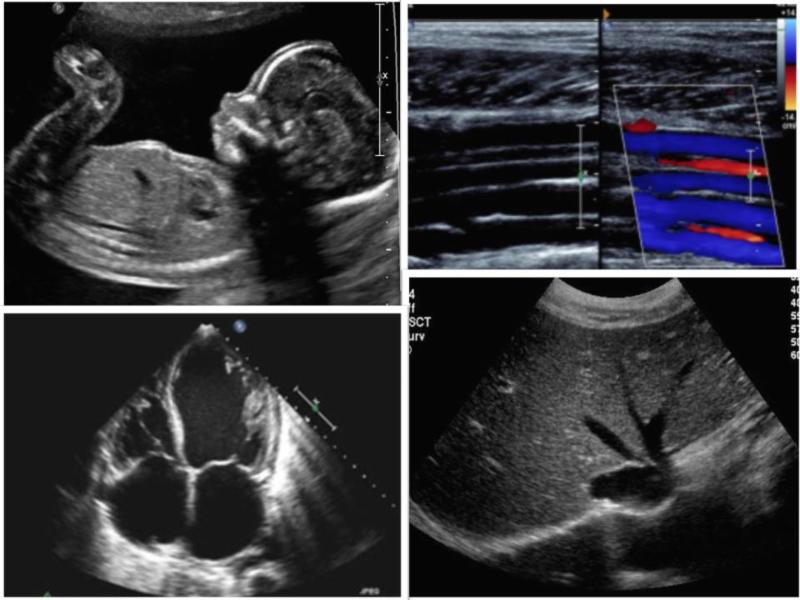

Concurrent sessions offering lectures in Echocardiography,

Vascular, Abdominal, Breast and Obstetrical topics.